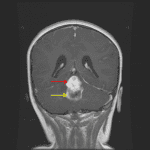

- Mixed solid and cystic mass centered in the fourth ventricle measuring 2.5 x 2.5 x 4 cm with a more solid enhancing component superiorly and a peripherally-enhancing cystic component inferiorly

- No corresponding restricted diffusion

- Associated effacement of the fourth ventricle and obstructive hydrocephalus with periventricular edema

- The “cyst with nodule” appearance is classic, but a minority of tumors do not demonstrate cystic components

- The solid component is usually hypoattenuating to brain on CT, T2 hyperintense, solidly enhancing, and does not demonstrate restricted diffusion